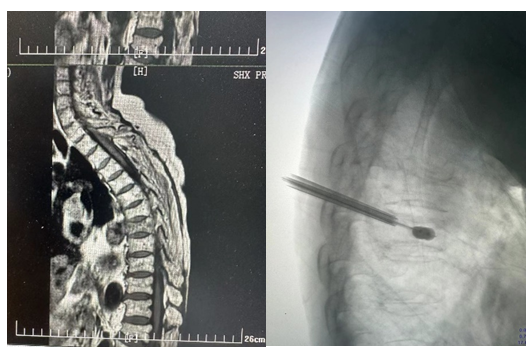

同时,骨科病院成功开展了西咸院区第一例脊柱微创手术。11月21日,骨科李全义主任医师在西咸院区接诊了一名81岁的老年患者,患者几天前不慎扭伤腰部,疼痛难忍,翻身和起床困难。经详细查体和影像学资料评估,以“胸椎压缩性骨折、骨质疏松症”收治入院。骨科病院刘时璋主任高度重视,多次指导。手术由李全义主任医师主刀,在急诊科王猛主治医师和手术室闵渝婷、张晨晰护士配合下顺利完成。术后患者生命体征平稳,背部疼痛明显好转,病情稳定,手术创口仅有0.5cm,全程没有疼痛感,患者及家属满意。